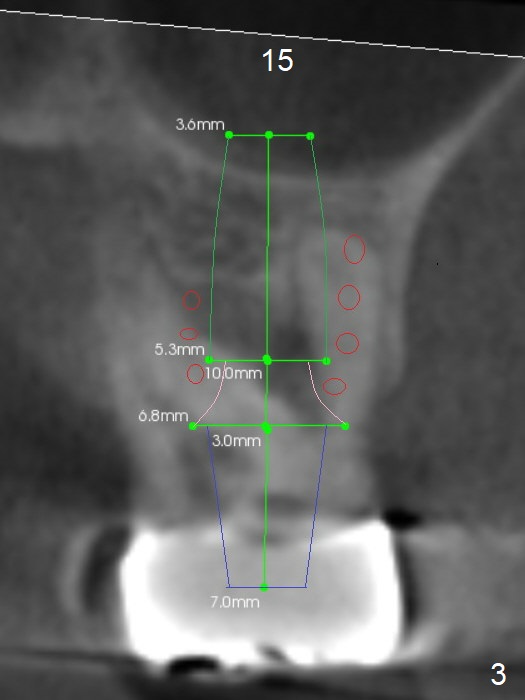

A 57-year-old man has food impaction in the upper left posterior sextant due to caries at #15 and 16 (Fig1). The bridge will be sectioned between 13 and 14. If the cantilever FPD of #12/13 is stable, place #14,15 implants in the normal mesiodistal position using surgical stent. Otherwise the implants should be distal so that there is space to distalize the tooth #13 orthodontically prior to #12 implant placement. Initial depths at #14 and 15 are 7 and 4 mm using IS and SCA kits. Find surgical stent.